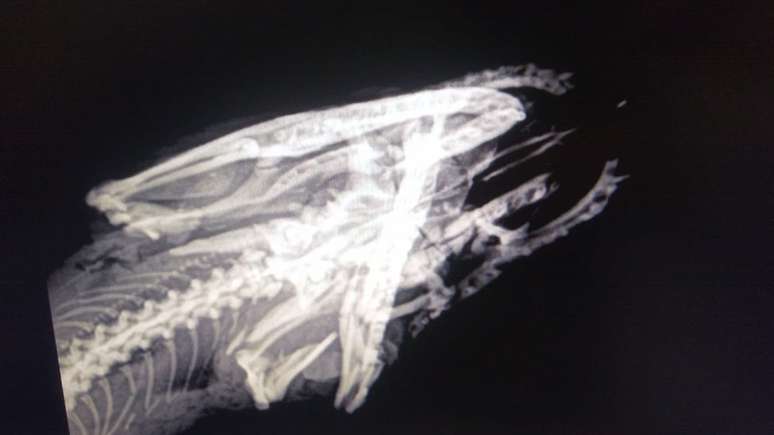

Raio-x mostra fratura na mandíbula de Santinha

Raio-x da jiboia

Ela foi medicada para reduzir sua dor extrema e os danos do ferimento, estabilizada e seguiu para uma rotina de exames radiograficos, para a posterior imobilização de sua mandíbula.

Durante os últimos três meses, Santinha passou por um longo processo de recuperação que incluiu uma série de cuidados, como medicação diária, limpeza da cavidade bucal, hidratação, alimentação forçada, aquecimento e exames constantes.

Ela também teve sua cabeça e mandíbula imobilizadas. Tratamentos alternativos que ajudam na cicatrização e reversão dos processos inflamatórios como o laser e a moxaterapia (técnica de acupuntura com calor), também foram usados.